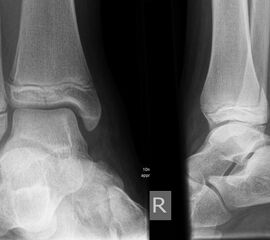

Fugengelenkfrakturen treten typischerweise vor dem 10. Lebensjahr auf, in einer Phase, in welcher die Wachstumsfugen noch weit offen sind. Dieser Frakturtyp betrifft fast ausschließlich den medialen Malleolus. Laterale Frakturen sind extrem selten, teilweise kommt es zu lateralen Bandverletzungen oder Fugenschaftfrakturen der distalen Fibula. Die Frakturlinie verläuft in einer Verlängerungslinie von der medialen Taluskante nach proximal. Häufig stellen sich Verletzungen des Innenknöchels im Röntgenbild schlechter dar, insbesondere wenn die Aufnahmen verdreht sind oder die Ebene der Fraktur bei geringer Dislokation verkippt zur Röntgenebene liegt. Besteht klinisch der geringste Hinweis auf eine Verletzung des Innenknöchels, muss aufgrund der Tragweite der Verletzung durch entsprechende Aufnahmen gegebenenfalls auch Schnittbildverfahren die Verletzung sicher diagnostiziert oder ausgeschlossen werden (Abb. 15).

Fugengelenkfrakturen können die Wachstumsfuge durchkreuzen (Abbildung 16a), ohne oder nur mit minimaler Beteiligung der Fuge sehr weit medial liegen (Abbildung 16b) oder durch die Fuge auslaufen (Abbildung 16c). Relevant für die Wachstumsprognose ist weniger die Form der Fraktur, sondern das Alter des Patienten zum Zeitpunkt des Traumas sowie das Ausmaß der Schädigung der Wachstumsfuge, wobei eine Korrelation mit dem Ausmaß der Dislokation besteht.